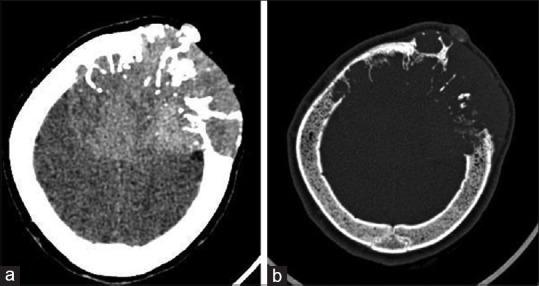

Plasmacytomas occur as lesions in soft tissue or bone. Skull vault plasmacytomas are rare lesions comprising 0.7% of all plasmacytomas. Workup for myeloma must be done in such cases to rule out multiple myeloma. Here, we report a case of a 63-year-old female who presented to us with a large skull vault swelling which appeared to mimic a parasagittal meningioma on imaging. Histopathological imaging revealed it to be a plasmacytoma. A retrospective review of the radiology revealed the characteristic "mini-brain appearance" in our case. Literature on the subject is also reviewed.

浆细胞瘤可表现为软组织或骨的病变。颅骨穹窿浆细胞瘤是罕见病变,占所有浆细胞瘤的0.7%。此类病例必须进行骨髓瘤检查以排除多发性骨髓瘤。在此,我们报告一例63岁女性,她因颅骨穹窿部巨大肿胀前来就诊,影像学检查显示其似乎类似矢状窦旁脑膜瘤。组织病理学检查显示为浆细胞瘤。对该病例的放射学回顾显示出其特征性的“迷你脑外观”。本文还对该主题的文献进行了综述。